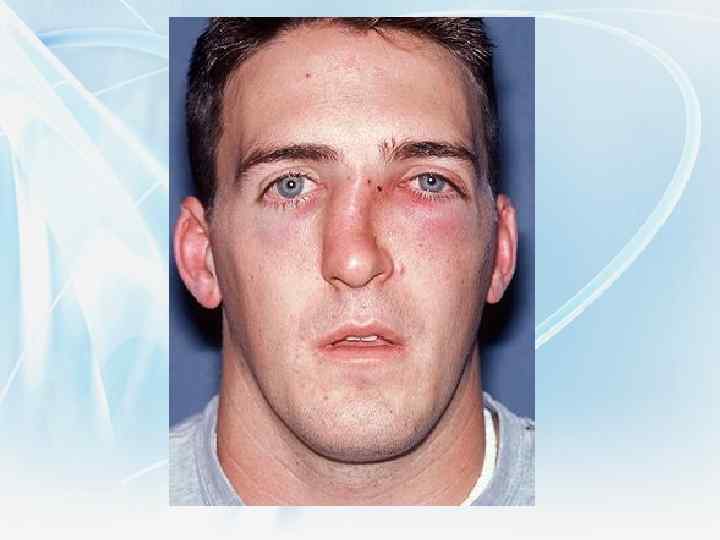

При травме отмечается повышение температуры, головная боль, носовые кровотечения, кровоизлияние в кожу носа и век, затрудненное носовое дыхание, нарушение обоняния, отек мягких тканей. Вследствие перелома костей носа с разрывом слизистой оболочки наблюдается эмфизема век. Нарушение обоняние более выражено в том случае, когда закрывается обонятельная щель или затруднено носовое дыхание. Снижение или полное отсутствие обоняния чаще наблюдается на стороне повреждения.

При травме отмечается повышение температуры, головная боль, носовые кровотечения, кровоизлияние в кожу носа и век, затрудненное носовое дыхание, нарушение обоняния, отек мягких тканей. Вследствие перелома костей носа с разрывом слизистой оболочки наблюдается эмфизема век. Нарушение обоняние более выражено в том случае, когда закрывается обонятельная щель или затруднено носовое дыхание. Снижение или полное отсутствие обоняния чаще наблюдается на стороне повреждения.